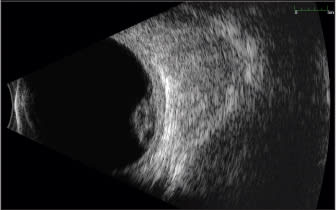

The B-scan ultrasound demonstrates an irregular mass.

The A-scan ultrasound indicates mixed medium and high internal reflectivity of the lesion. Ultrasonographic features help make the diagnosis of a choroidal hemorrhage rather than a choroidal melanoma.